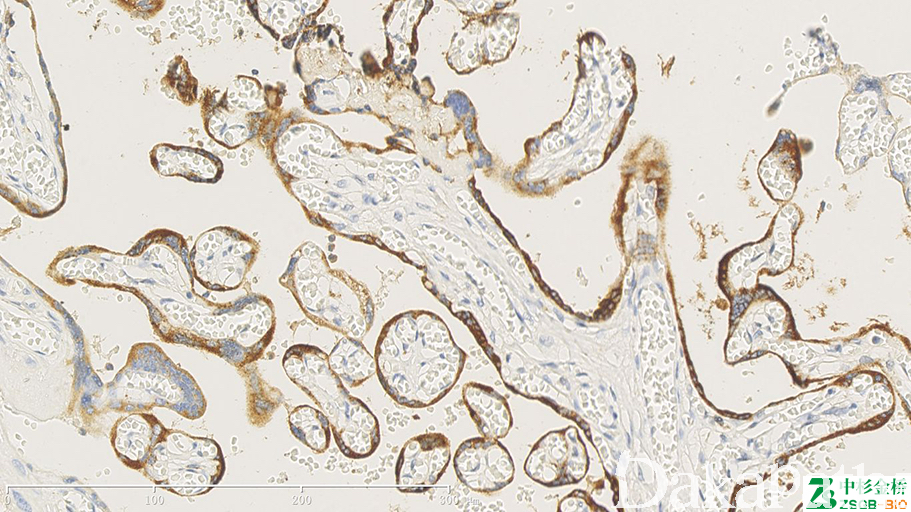

- Cytoplasmic stain; relatively specific for choriocarcinoma or syncytiotrophoblasts

几乎全部阳性(≥95%的病例阳性): 子宫内膜绒毛膜癌